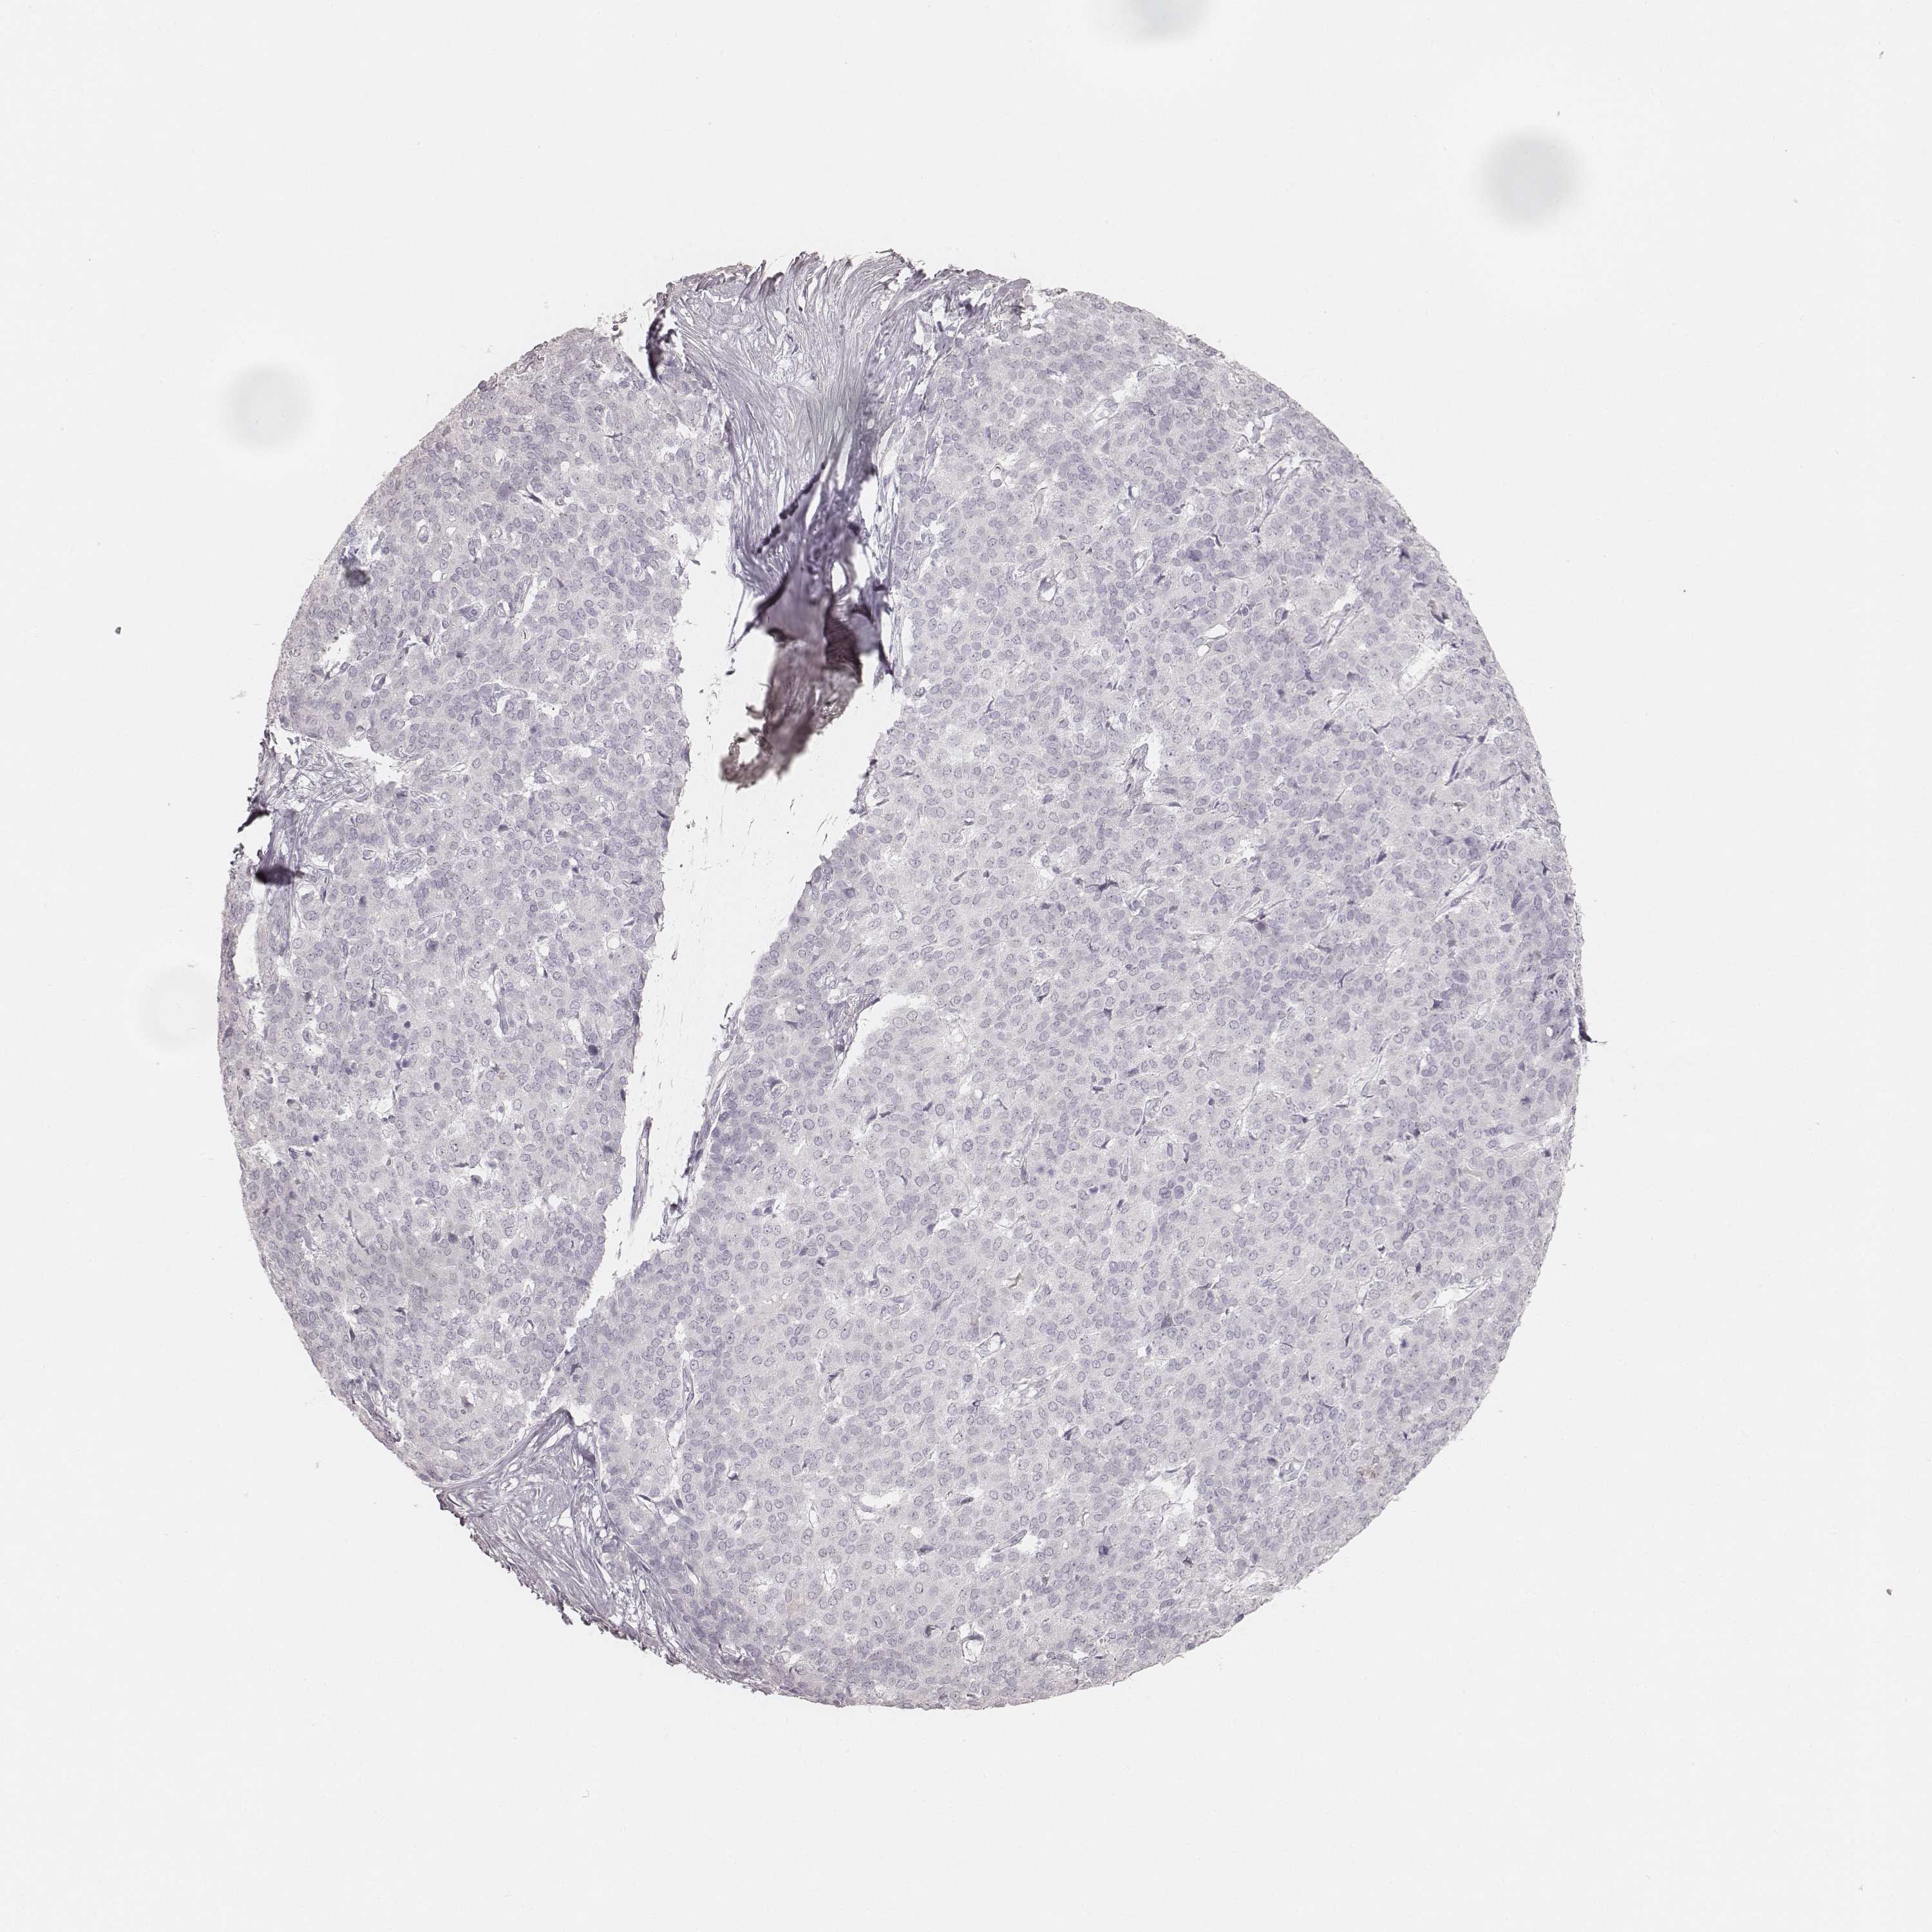

LIVER CANCER - Protein expressioni

A mouse-over function shows sample information and annotation data. Click on an image to view it in a full screen mode. Samples can be filtered based on level of antibody staining by selecting one or several of the following categories: high, medium, low and not detected. The assay and annotation is described here.

Note that samples used for immunohistochemistry by the Human Protein Atlas do not correspond to samples in the TCGA dataset.

Antibody stainingi

Antibody staining in the annotated cell types in the current human tissue is reported as not detected, low, medium, or high, based on conventional immunohistochemistry profiling in selected tissues. This score is based on the combination of the staining intensity and fraction of stained cells.

Each image is clickable and will lead to virtual microscopy that enables deeper exploration of all samples and also displays staining intensity scores, fraction scores and subcellular localization as well as patient and tissue information for each sample.

Antibody HPA049550

Antibody HPA055194